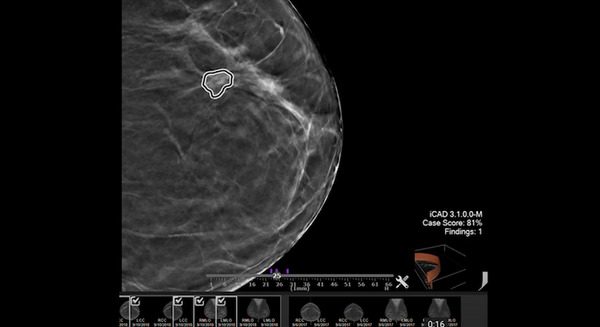

オランダがん研究所 NVIDIA AI Enterpriseで腫瘍の位置を特定できるディープラーニングモデルを構築

NVIDIAはオランダがん研究所とヘルスケア企業のVyasa、iCADおよびRhino HealthがNVIDIA AI Enterpriseのソフトウェアスイートを使用して、エンドツーエンドのAIワークロードをいち早く実現したことを発表した。

解像度の向上で腫瘍のサイズや位置をより正確に特定